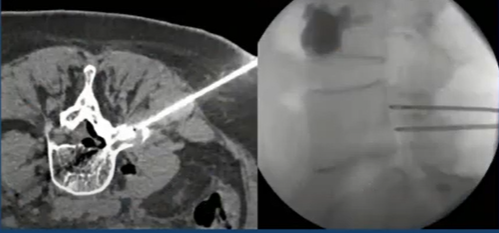

Interventionnelle osseux

VALKENBORGH C. - ULG

Année académique 2020-2021

Vasculaire Interventionnelle DES SPECIALITE